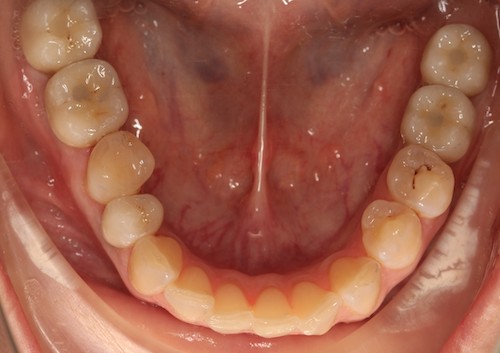

Рис.8 Концевые дефекты.Поставлены импланты.Мост поставить нельзя.